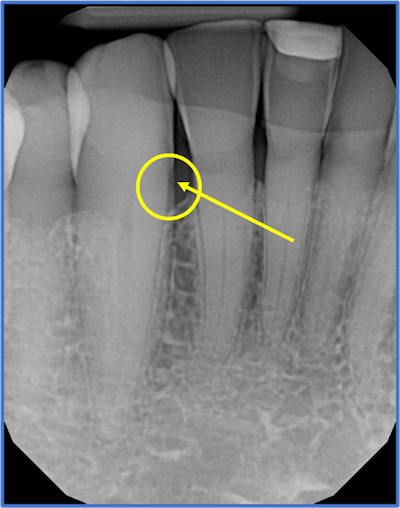

After his detailed evaluation, he determined my overall mouth health was excellent. But he noticed a small area of soft decay on the side of the root of my lower right cuspid (tooth #27) between the cuspid and lateral tooth. It was not significant on the x-ray, but he diagnosed it with a dental instrument.

On November 2, 2021, I had a full-mouth series of dental x-rays confirming root decay on the mesial of #27 and evaluating other areas in my mouth. My dentist mechanically removed the soft decay in the area and placed ozone to kill the bugs.